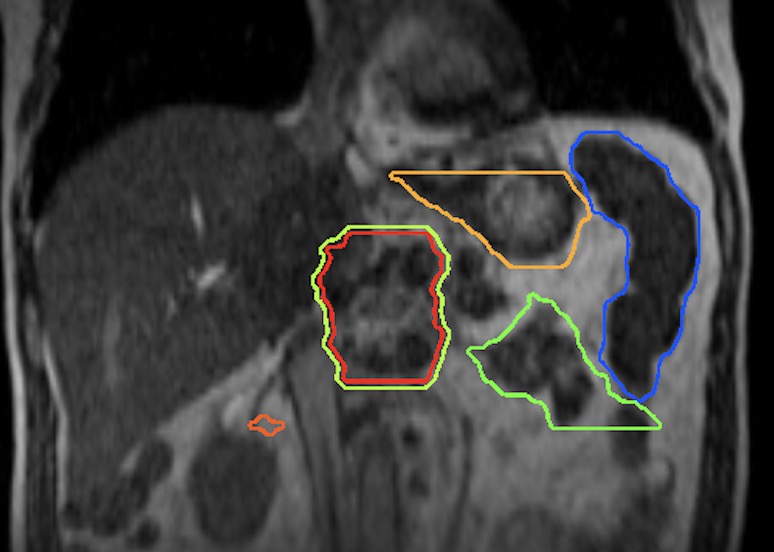

Treating patients with localized, solid tumors near critical organs in the body? Target them with proton therapy, reducing side effects now and in the future.